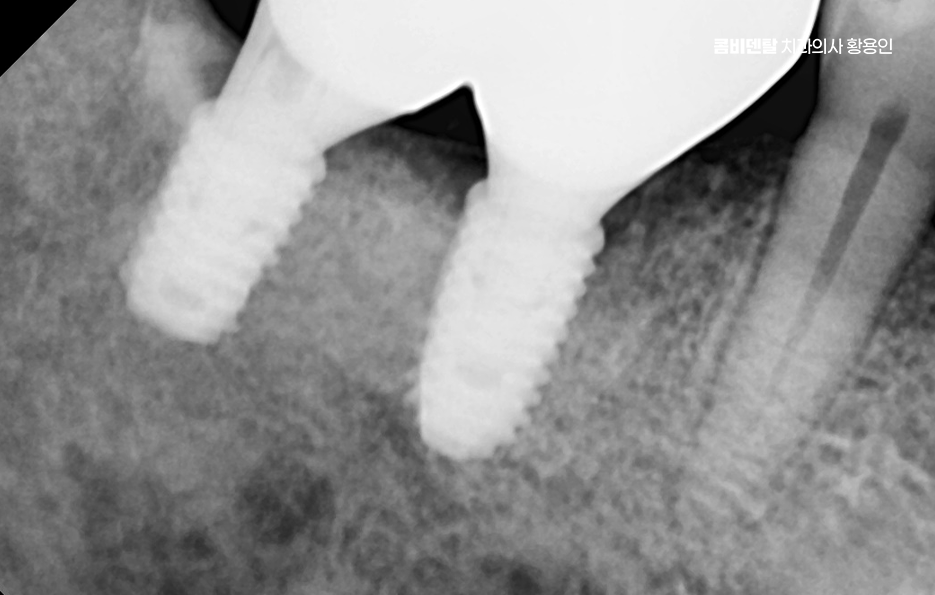

임플란트를 심을 잇몸 뼈가 충분하다면 바로 식립이 가능하지만 치아를 빼고 오래 방치한 경우에는 뼈가 흡수되어 부족할 수 있으며 이때는 뼈이식을 먼저 하거나 동시에 진행하고 어금니는 씹는 힘이 강하기 때문에 초기 고정이 단단해야 하며 유지까지 고려할 때 교합의 정교한 맞물림이 중요한 부위라고 할 수 있었어요

어금니 임플란트 과정에서 수술 당일에는 국소마취 후 잇몸을 절개하거나 최소 절개로 접근해 뼈에 임플란트를 식립하며 수술 후에는 일정 기간 골유착을 기다리는데 임플란트와 뼈가 단단히 결합하는 과정이라 할 수 있었어요

골유착이 완료되면 지대주를 연결하고 본을 떠서 최종 보철물을 제작하며 어금니 크라운은 강도와 교합 조화를 동시에 고려해 제작하는데 씹는 힘이 집중되는 부위이기 때문에 높이와 접촉점 조정이 중요하며 교합이 맞지 않으면 나사가 풀리거나 보철물에 문제가 생길 수 있어서 장착 후에도 교합 점검 및 정기적인 검진, 스케일링 등의 관리가 중요할 수 있어요